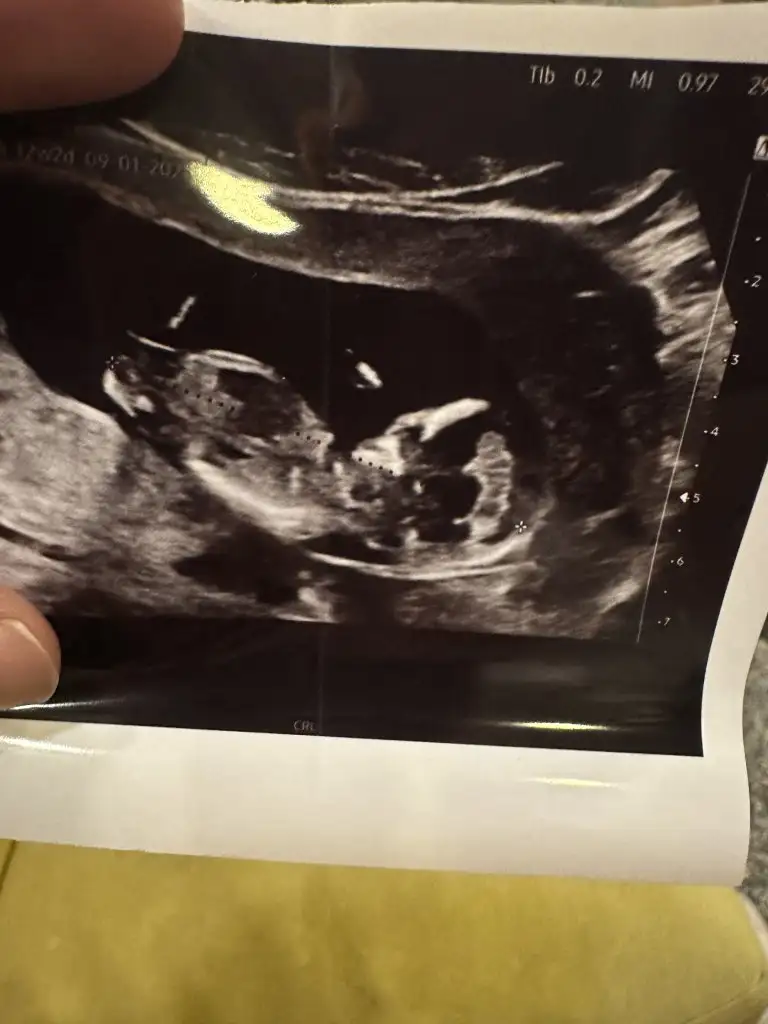

Banada bakar mısınız lütfenMerhaba canım nuba göre erkek duruyor

Sanki çıkıntısı var erkek gibi duruyorBanada bakar mısınız lütfen

Ama çok erkek gibi duruyo yaBuda bugünün ultrasonu doktor kız dedi ama gören erkek diyor sizce ne